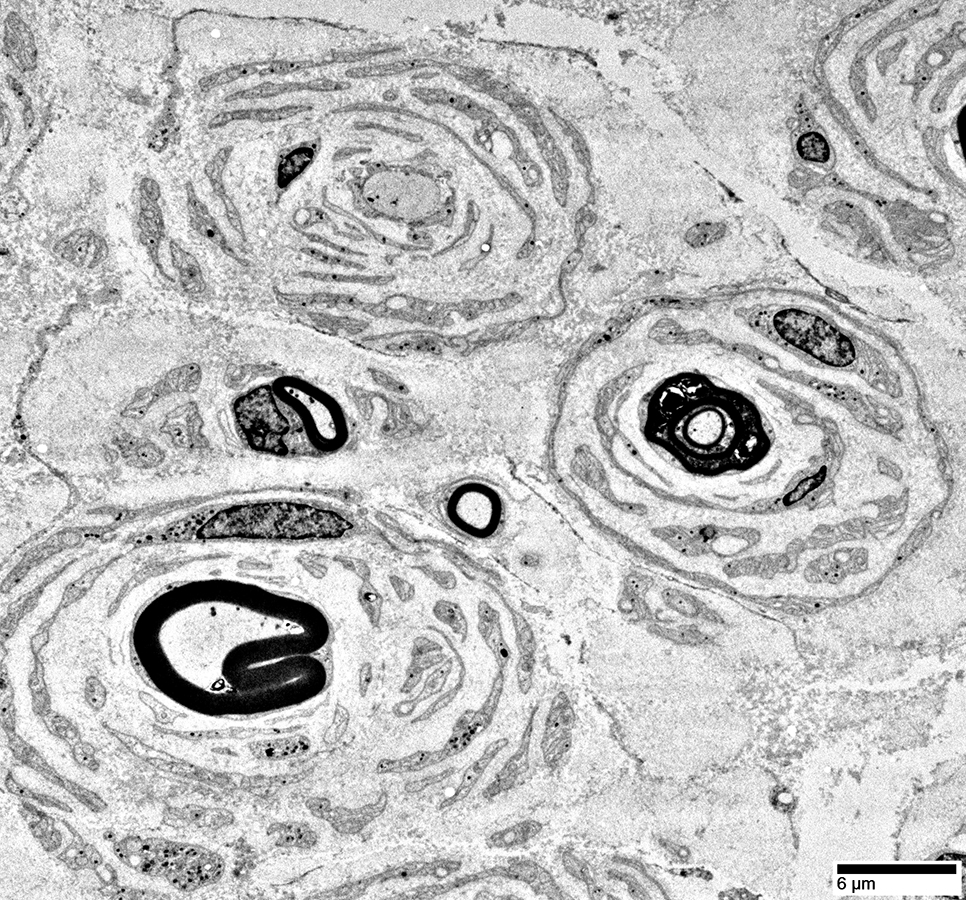

Electron micrograph: From Robert Schmidt MD

|

Onion Bulbs: Large, Late

Toluidine blue stains of plastic nerve sections

Onion bulbs, Large

Multiple Connective tissue layers

& Schwann cell processes

around thinly myelinated axons.

Onion bulbs may contain 0, 1,

or several, axons.